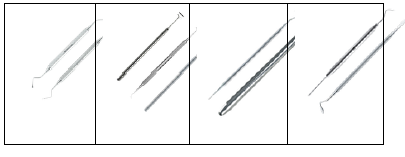

Considere as imagens abaixo na sequência:

Os instrumentais indicados representados na figura, são:

Assinale a alternativa CORRETA: